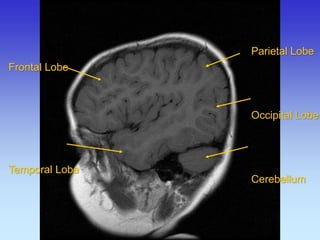

Frontal Lobe Lateral Sulcus

Parietal Lobe

Temporal Lobe

Frontal Lobe

Occipital

Lobe

Cerebellum